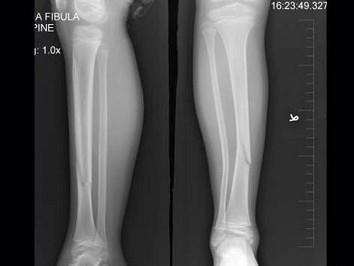

问题 8岁女性患者,因外伤后致右胫骨骨折,下列描述正确的是 ( )

选项 A、对位对线差 B、以上都不正确 C、对位差,对线好 D、对位对线好 E、对位好,对线差

答案 E